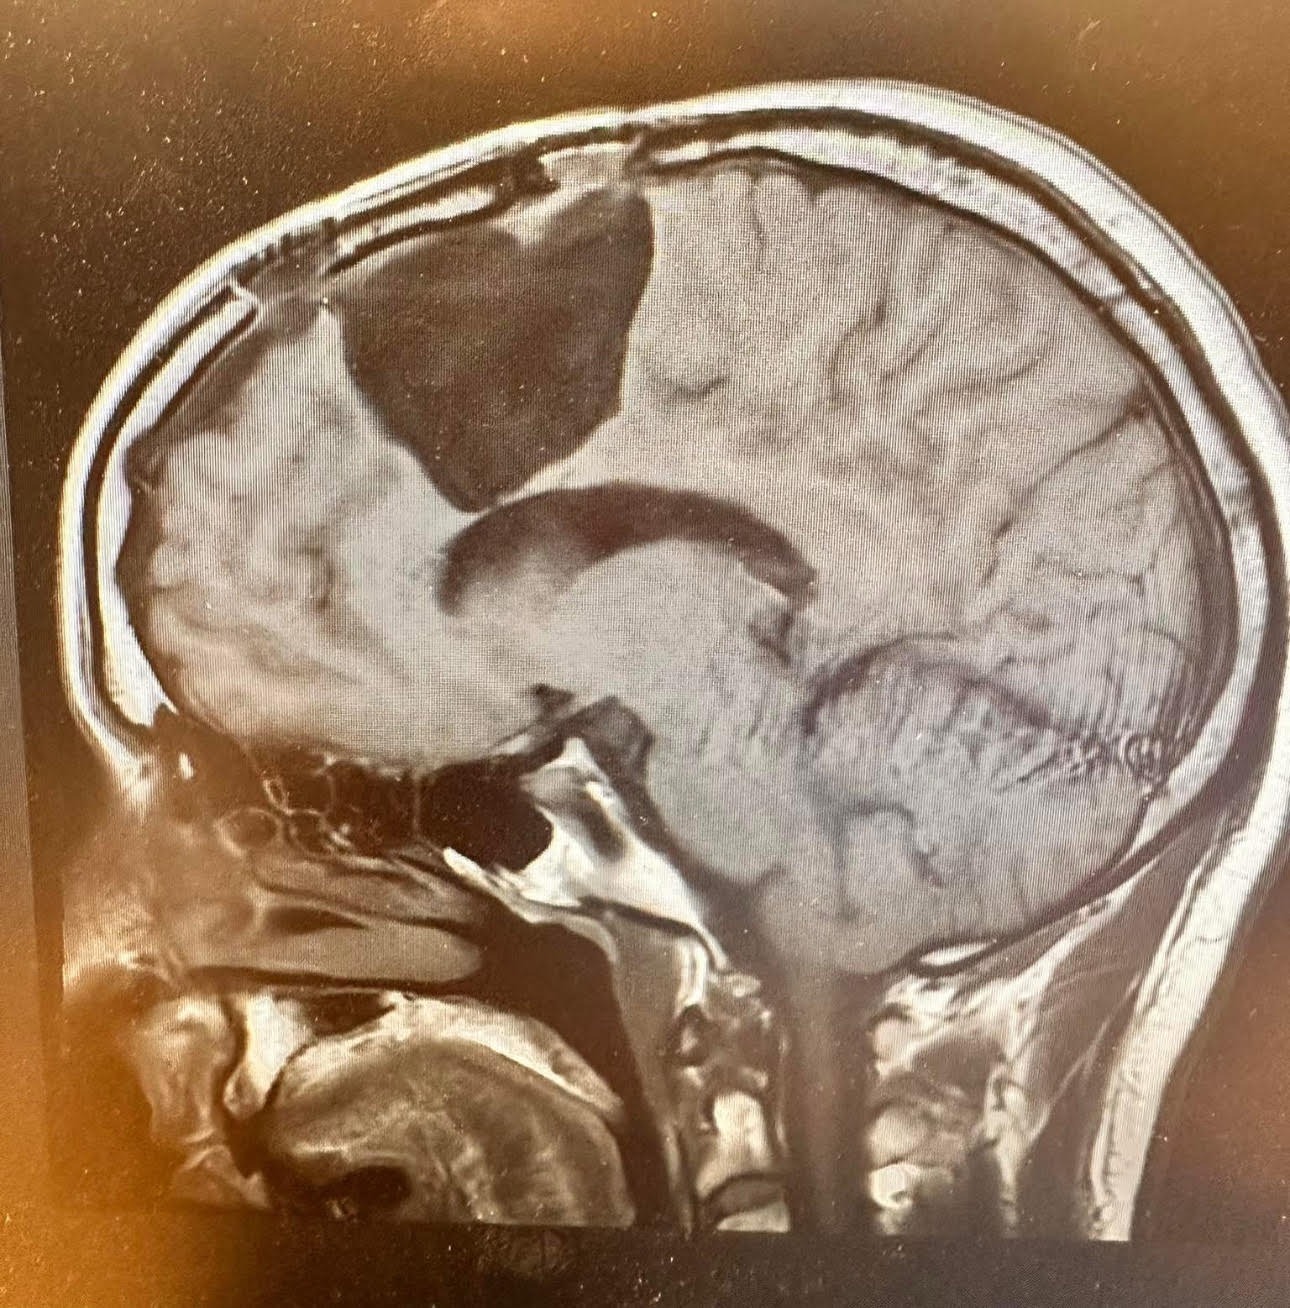

April 8, 2025: Just weeks after surgery, an MRI revealed another recurrence — a 1.7 x 0.6 x 1.0 cm nodular mass in the surgical cavity.

April 11, 2025: Duke University confirmed this second recurrence.